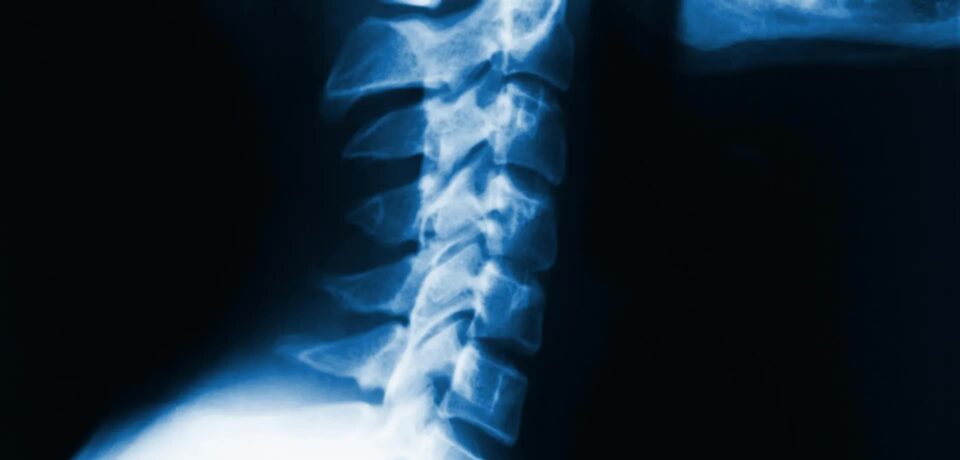

schema_cervicale

Fizioterapia dhe Hernia Cervikale

Fizioterapia dhe Hernia Cervikale Çfarë është Hernia Cervikale? Hernia cervikale është një problem që ndodh kur disku ndërvertebral në qafë del jashtë vendit të tij normal dhe shtyp nervat përreth. Kjo mund të shkaktojë: Si ndihmon Fizioterapia? Fizioterapia është një nga mënyrat më të sigurta dhe efektive për të trajtuar…